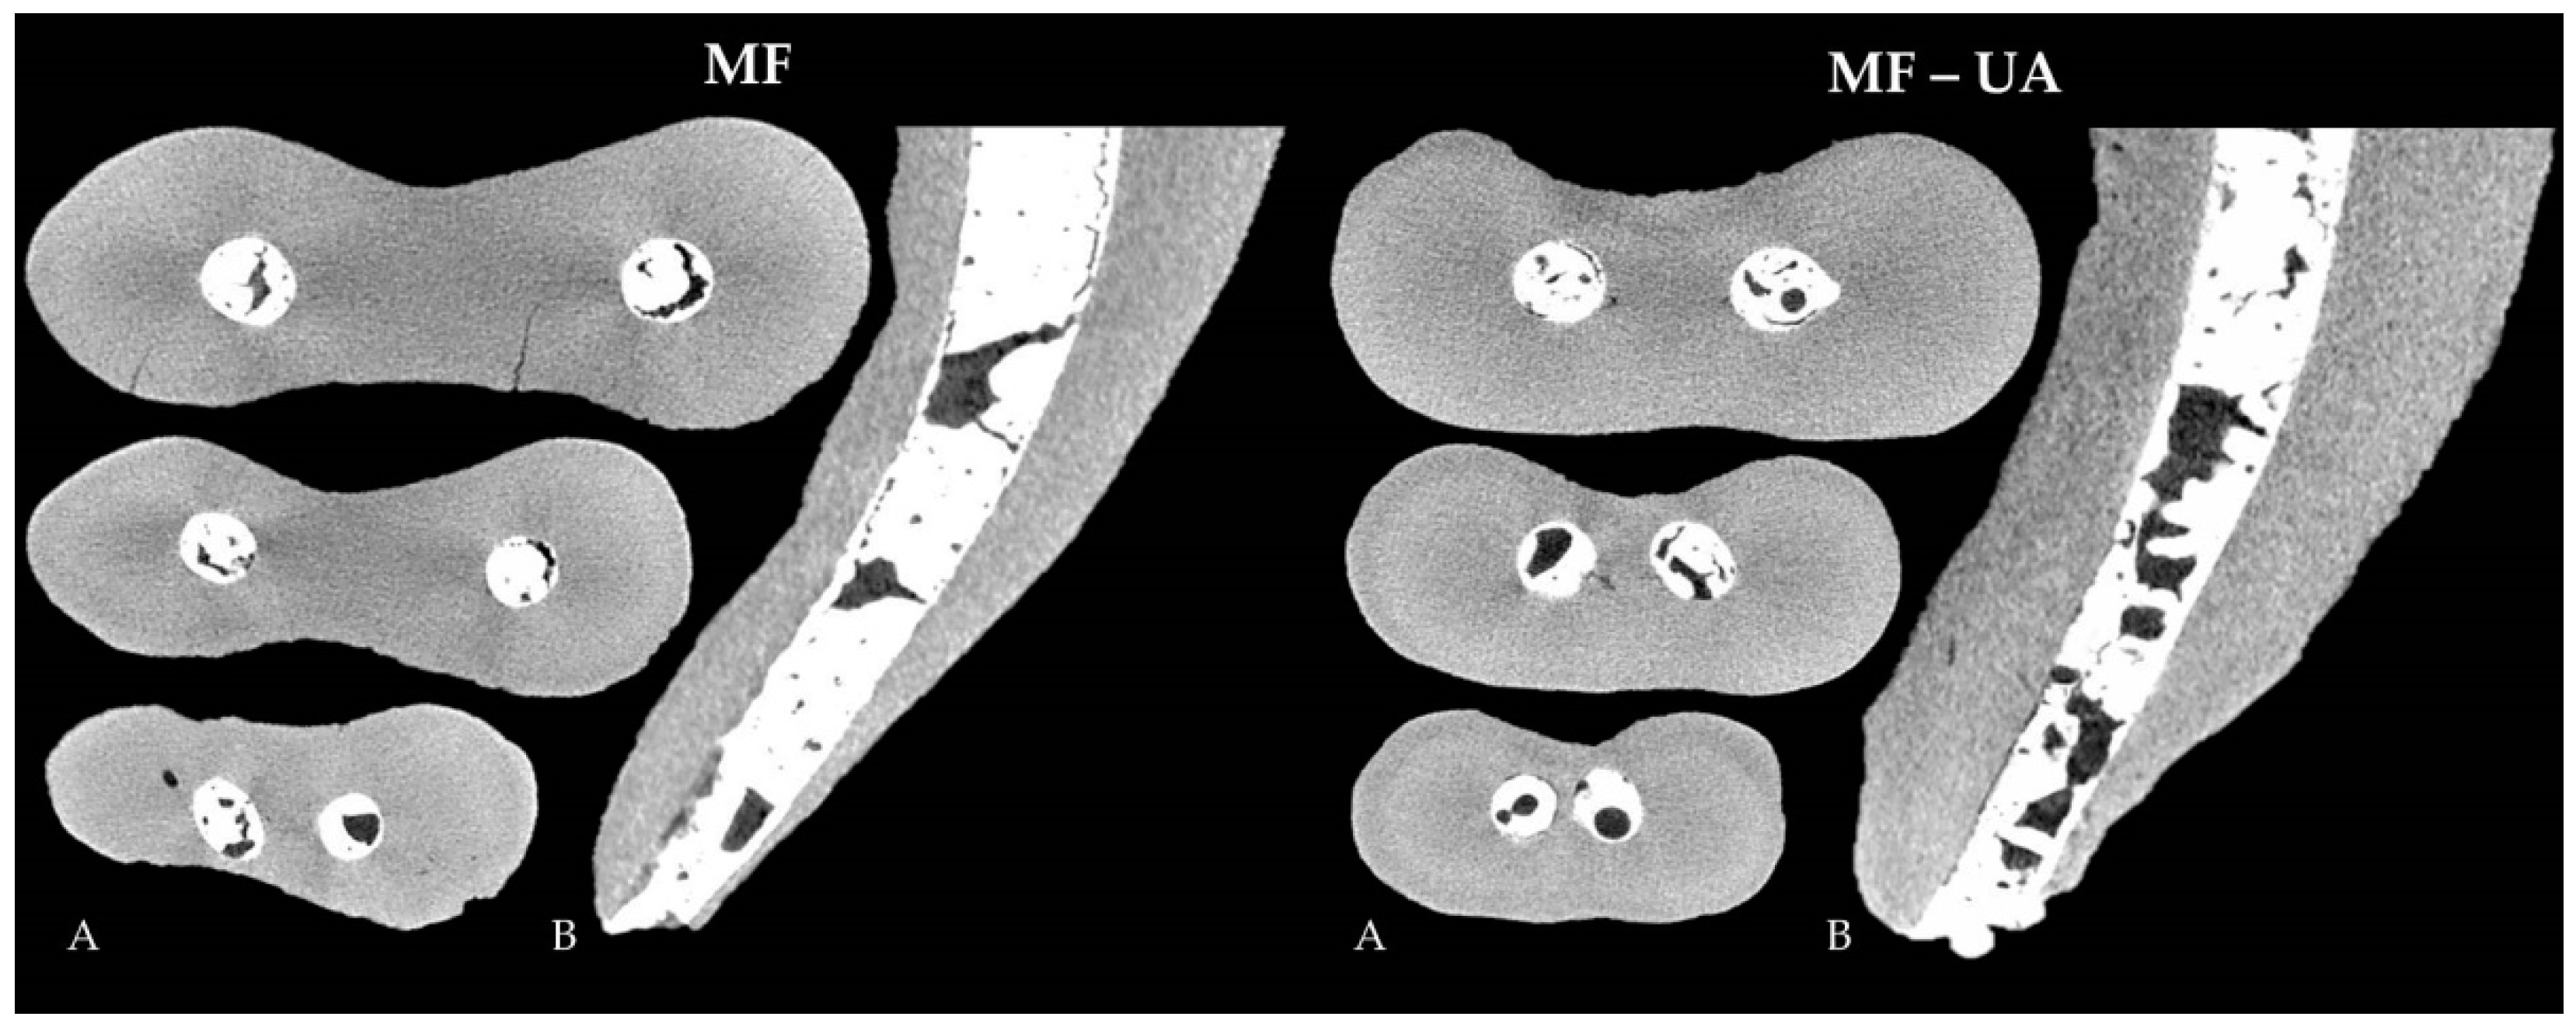

- MF group—the root canals were filled with MTA Flow cement. A total of 0.19 g of powder and 3 drops of liquid were mixed according to the manufacturer’s recommendations to get a thin consistency of the cement. The mixed material was inserted into the clear Skini syringe, and the flowability of the material was checked by extruding the small amount of the cement through the attached 29-G NaviTip needle. The filling material was delivered into the root canal by slowly pressing the plunger of the syringe and withdrawing the tip, which was inserted 2 mm short of the perforated apex.

- MF-UA group—the root canals were filled with MTA Flow cement using ultrasonic agitation. The filling material was prepared and injected into the root canal in the same manner as in the MF group. Afterwards, the Ultrawave ET25 ultrasonic tip was directly inserted into the root canal and MTA Flow cement 2 mm short of the perforation site and activated for 10 s at the 28–36 kHz frequency and the power described previously.